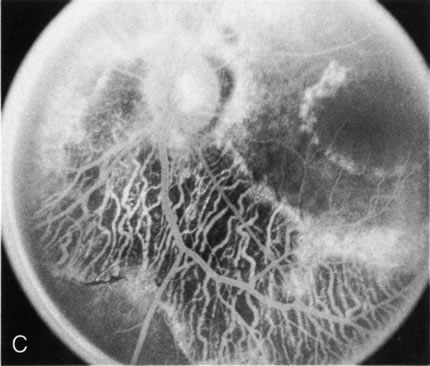

In the early stages of choroideremia, before choroidal atrophy is funduscopically obvious and when the picture resembles RP, FA indicates diffuse choroidal atrophy throughout the entire retina. Only the macular area remains preserved (Fig. 4A and B).

Fig. 4. Choroideremia and choroideremia carrier. A. The choroidal atrophy in this affected male is not apparent in the fundus. B. However, the angiogram shows diffuse atrophy of the choriocapillaris with persistent visualization of the larger choroidal vessels. C. This carrier female has peripapillary choroidal atrophy and diffuse pigment mottling. D. The patchy areas of focal choroidal atrophy that occasionally occurs in carriers is evident on angiography.

The typical carrier female, with focal or diffuse pigment mottling, does not show choroidal atrophy. However, a few carrier females have a more severe form with focal areas of choroidal atrophy. The presence of these areas, and possible progression, can be documented by FA (Fig. 4C and D). These carriers exhibit a mosaicism, which is explained by the Lyon hypothesis of random X-chromosome inactivation.